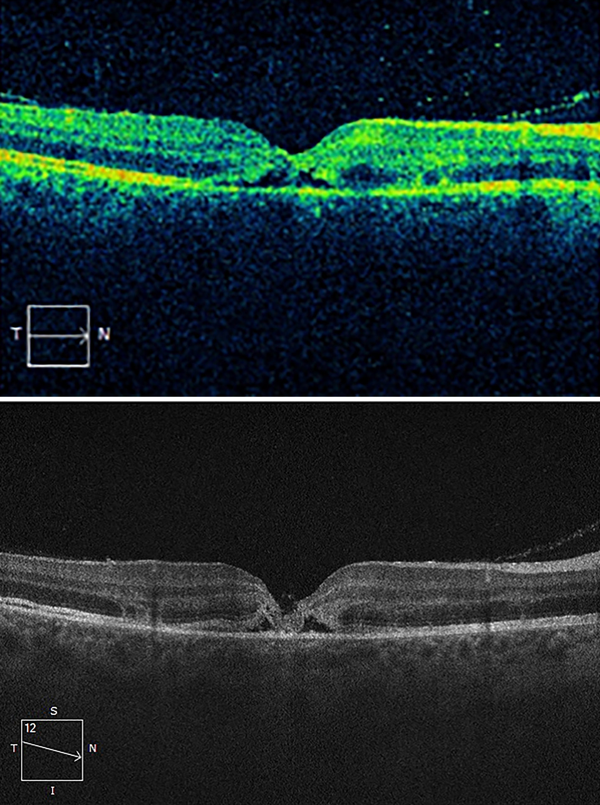

Se toma una ecografía en OD donde se observa retina aplicada e imagen compatible con hemorragia superior. Se decide realizar una tomografía de coherencia óptica (OCT Cirrus 5000) en el momento de la consulta y luego hacer un seguimiento los días posteriores del traumatismo con OCT. En el primer estudio realizado se puede observar un agujero macular de espesor completo (fig. 2) y un espesor retinal de 242 micras.

Figura 2. OCT que muestra agujero macular traumático de espesor completo.

Se cita a control al paciente 36 horas después del traumatismo y se repite la OCT observándose el agujero macular traumático en vías de cierre (fig. 3) con un espesor retinal de 242 micras. En el momento de la consulta se dictamina que la AV en OD se encontraba en visión cuenta dedos a 2 metros y la PIO se constató en 16 mmHg.

En la tercera consulta, 5 días después del traumatismo, se constata que la visión continuaba sin modificaciones y se observa en OCT el cierre espontáneo del agujero macular (fig. 4) con un espesor retinal de 204 micras.

Figura 3. Agujero macular en vías de cierre dos días posteriores al traumatismo.

Figura 4. Agujero macular cerrado 5 días posteriores al traumatismo.